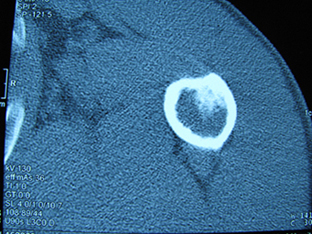

标题: X6404B:肱骨骨质破坏(CT片) [打印本页]

标题: X6404B:肱骨骨质破坏(CT片)

男,50岁,左肩部轻微疼痛,活动不便5个月就诊,近十天加重,无红肿热,间断理疗治疗无好转,既往5个月前左肩轻微拉伤史

骨巨?动脉瘤样骨囊肿?

内生软骨瘤。

内生软骨瘤。

内生软骨瘤?-----------

年纪大了,先要排除转移瘤。

髓腔内软组织肿块并斑片状钙化,考虑高分化软骨肉瘤可能性大。

考虑骨巨或动脉瘤样骨囊肿。

内生软骨瘤可能性大,期待结果。

孤立性骨囊肿。

内生软骨瘤可能性大

其内可见钙化,考虑软骨源性肿瘤,内生软骨瘤可能

但由于年龄较大,恶性软骨肉瘤待排

肱骨头内巨大软组织肿块并斑片状钙化,内生软骨瘤?骨巨细胞瘤?软骨粘液样纤维瘤?期待结果!

髓腔内软组织肿块并斑片状钙化,考虑高分化软骨肉瘤可能性大。

内生软骨瘤可能性大

肱骨头内巨大软组织肿块并斑片状钙化,内生软骨瘤?骨巨细胞瘤?软骨粘液样纤维瘤?期待结果

考虑内生软骨瘤?骨巨细胞瘤?

内生软骨瘤?骨巨细胞瘤?

先要排除转移瘤。